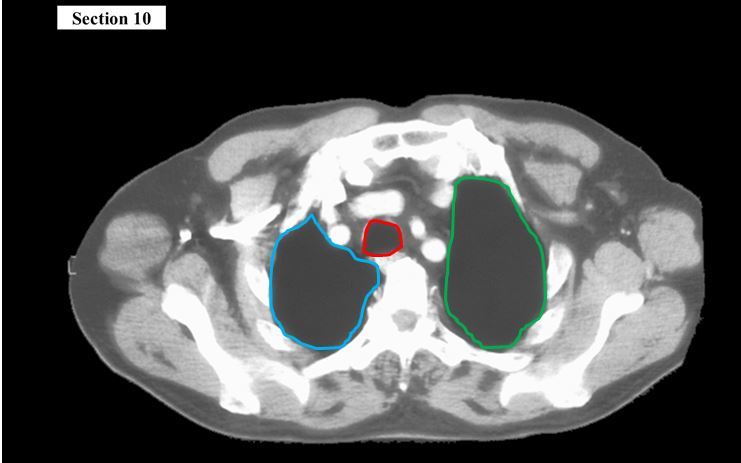

10

Q

The green space is the _____

The yellow structure is the _____

The red structure is the _____

A

pleural cavity

trachea

esophagus

How well did you know this?